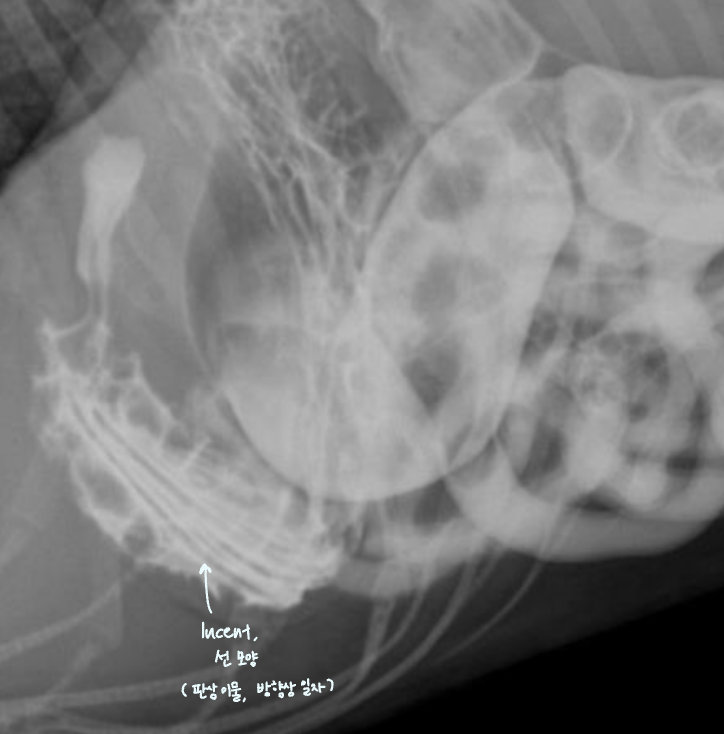

์ ๋ฆฝ์ ๋น๋

| Benign prostatic hyperplasia (BPH) |

|---|

| (๋ฐฐ์ฐ์ง ์์์ง๋ง ์กฑ๋ณด์ ๋ฑ์ฅํ๋ ๋ณ๋ช

.) ์ ๋ฆฝ์ ๋น๋์ ์ํด - ์๋๊ฐ ์๋ฐ๋์ด ๋ฐฉ๊ด์ cranial margin์ด ํฝ๋๋จ. - ์ ๋ฆฝ์ ๊ณผ ๋ฐฉ๊ด ์ฌ์ด์ ์ง๋ฐฉ์ ๊ฒฝ๊ณ๊ฐ ์๊ฒจ ์ผ๊ฐํ ๋ชจ์์ radiolucentํ ์์์ด ๋ํ๋จ. ![]() |